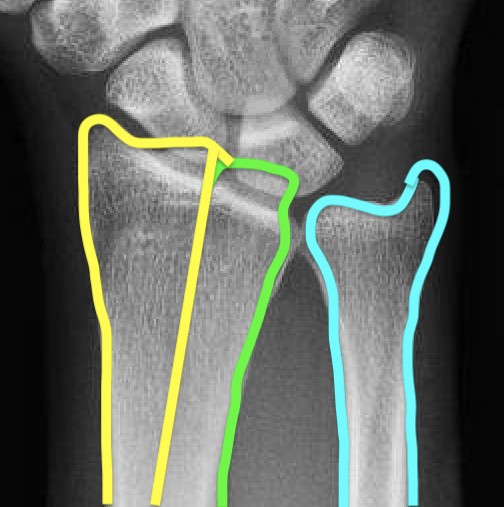

Distal Radius Angles

- radial volar tilt 11°

- radial inclination  22°

- radius is 11 mm longer than ulna

- ulna variance 2mm positive on average

Distal Radius NormalNormal Radial InclinationNormal Radial Length